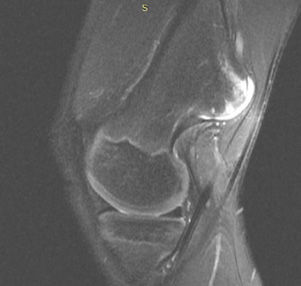

Kemiğin selim-agresif tümörü olarak kabul edilir. Genç erişkinde osteolitik karakterde kemik tümörüdür. Uzun kemiklerin ekleme yakın uç kısmından çıkabilir. Hastalar tümör bölgesinde devamlı ve giderek artan inatçı bir ağrı ve şişlik ile başvururlar.Sadece küretaj yapılan hastalarda yüksek lokal nüks yanında akciğer metastazı yapma potansiyeli olduğundan lokal agresif tümör olarak kabul edilir. Ama bu metastazlar ölümcül değildir.Diz eklemi en sık tutulan bölgedir. Diğer sık tutulan bölge el bileğidir. Kemik korteksini harap ederek yumuşak dokulara yayılım gösterebilir. Tanı için biyopsi şarttır. Brown tümörü ile ayırıcı tanısı yapılmalıdır. Tanı esnasında akciğer tomografisi çekilmelidir.

Tedavide genişletilmiş küretaj ve adjuvan ajanlarla kalan tümör hücreleri öldürülmeye çalışılır. Adjuvan ajan olarak; sıvı azot, alkol, fenol, argon koter, kriyoterapi, yüksek hızlı burr ve sementleme (kemik çimentosu) uygulanır. Eklemin tutulduğu vakalarda eklem feda edilir,protez veya artrodez uygulanabilir. Rezeksiyonun zor olduğu olgularda denosumab kullanılması önerilmektedir.Hastaların lokal nüks ihtimaline karşı 10 yıl süre ile takibi yapılmalıdır.